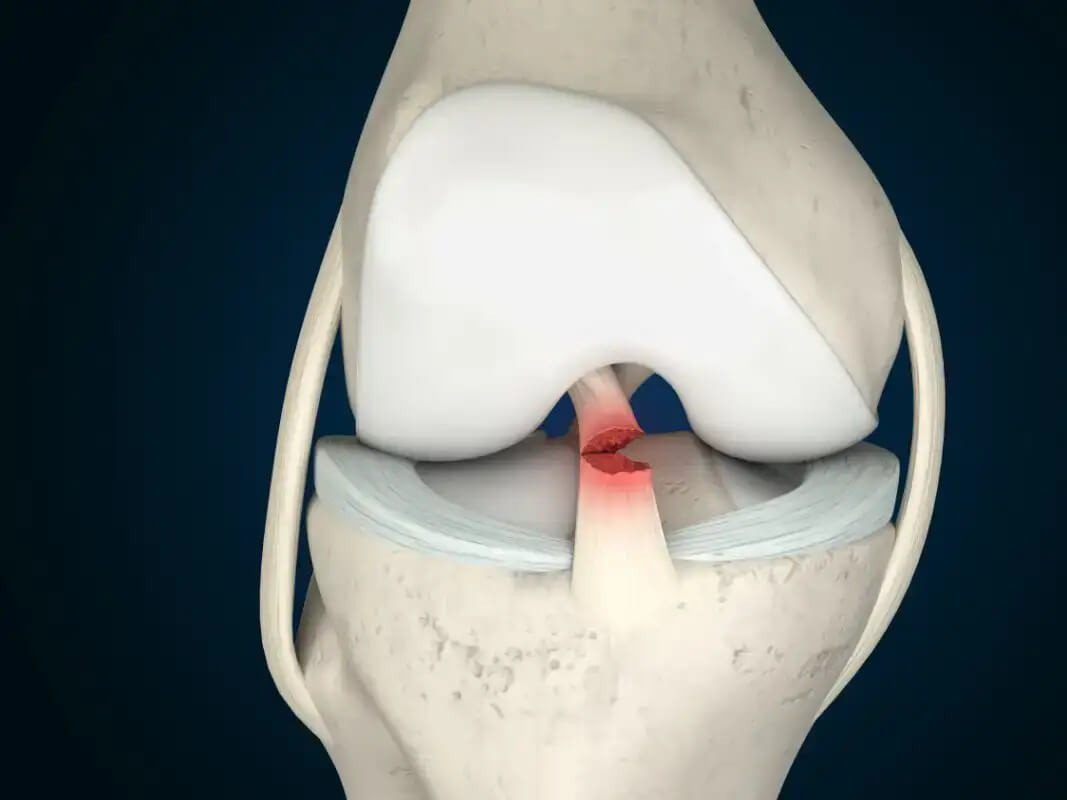

Разрыв передней крестообразной связки

Разрыв передней крестообразной связки (ПКС) – распространенная проблема, с которой обращаются в отделение травматологии. Разрывы ПКС занимают 2 место (после травм мениска) среди всех травм коленного сустава и 1 – среди травм его связочного аппарата (46-50% всех случаев). Передняя крестообразная связка ограничивает смещение голени кпереди относительно бедра, вместе с задней находятся внутри суставной капсулы коленного сустава.

ПКС образована тремя пучками плотных коллагеновых волокон, которые не могут растягиваться, поэтому при чрезмерных нагрузках происходит нарушение целостности волокон, их связи друг с другом (разволокнение передней крестообразной связки), либо отрыв связки от суставной поверхности кости.